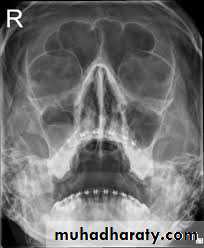

The paranasal sinuses

The paranasal sinuses are cavities found in the interior of maxilla , frontal, sphenoid, and ethmoid bones.They are lined with mucoperiosteum and filled with air; they communicate with the nasal cavity through relatively small apertures. The maxillary and sphenoidal sinuses are Present in a rudimentary form at birth; they enlarge appreciably after the eight year and become fully formed in adolescence.

The maxillary sinus is pyramidal in shape and located within the body of the maxilla behind the skin of the cheek. The roof is formed by the floor of the orbit, and the floor is related to the roots of the premolars and molar teeth. The maxillary sinus opens into the middle meatus of the nose through the hiatus semilunaris .Frontal sinuses

The two frontal sinuses are contained within the frontal bone . they are separated from each other by a bony septum. Each sinus is roughly triangular, extending up ward above the medial end of the eyebrow and backward into the medial part of the roof of the orbit. Each frontal sinus opens into the middle meatus of the nose through the infundibulum.Sphenoidal sinuses

The two spheniodal sinuses lie within the body of the sphenoid bone. Each sinus opens into the sphenoethmoidal recess above the superior concha.Ethmoid sinuses

The ethmoidal sinuses are anterior , middle, and posterior and they are contained with the ethmoid bone, between the nose and the orbit . they are separated from the latter by a thin plate of bone so that infection can readily spread from the sinuses into the orbit , the anterior sinuses open into the infundibulum; the middle sinuses open into the middle meatus, on or above the bulla ethmoidalis; and the posterior sinuses open into the superior meatus.